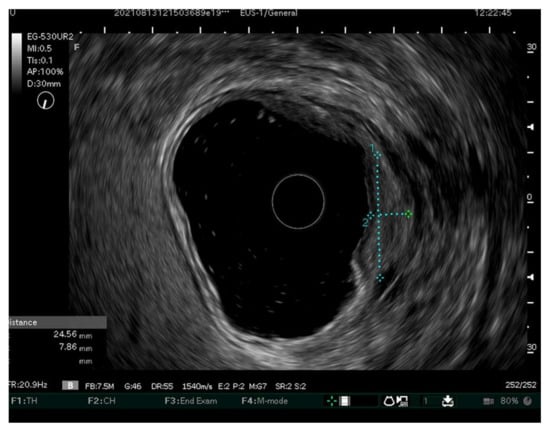

- Tsujii, Y.Y.; Hayashi, Y.; Ishihara, R.; Yamaguchi, S.; Yamamoto, M.; Inoue, T.; Nagai, K.; Ogiyama, H.; Yamada, T.; Nakahara, M. Diagnostic value of endoscopic ultrasonography for the depth of gastric cancer suspected of submucosal invasion: A multicenter prospective study. Surg. Endosc. 2022. [Google Scholar] [CrossRef]